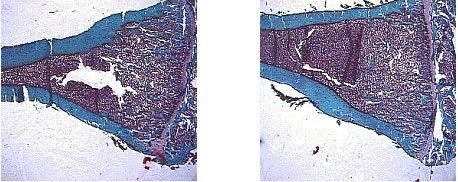

(1) Preventive effects of cervine horn extract

Postmenopausal estrogen deficiency will

occur osteoporosis. It may one of the leading cause of

senile diseases. In Korea, ERT (estrogen replacement therapy)

has been established to postmenopusal osteoporosis since

a decade. We investigated corvine horn extract(CHE) as

a natural resource of osteoporosis prevention. We administered

CHE to ovariectomized and osteoporotic mouse, and then

analyzed by bone histomorphometry. Finally, we found CHE

could prevent osteoporosis on estrogen deficient state,

but not treated previously made osteoporosis. |

Figure 1. control (left) mouse revealed

osteoporosis 12 weeks passed after ovariectomy, but CHE

administered (right) mouse showed with ovariectomy showed

no osteoposis at all. |